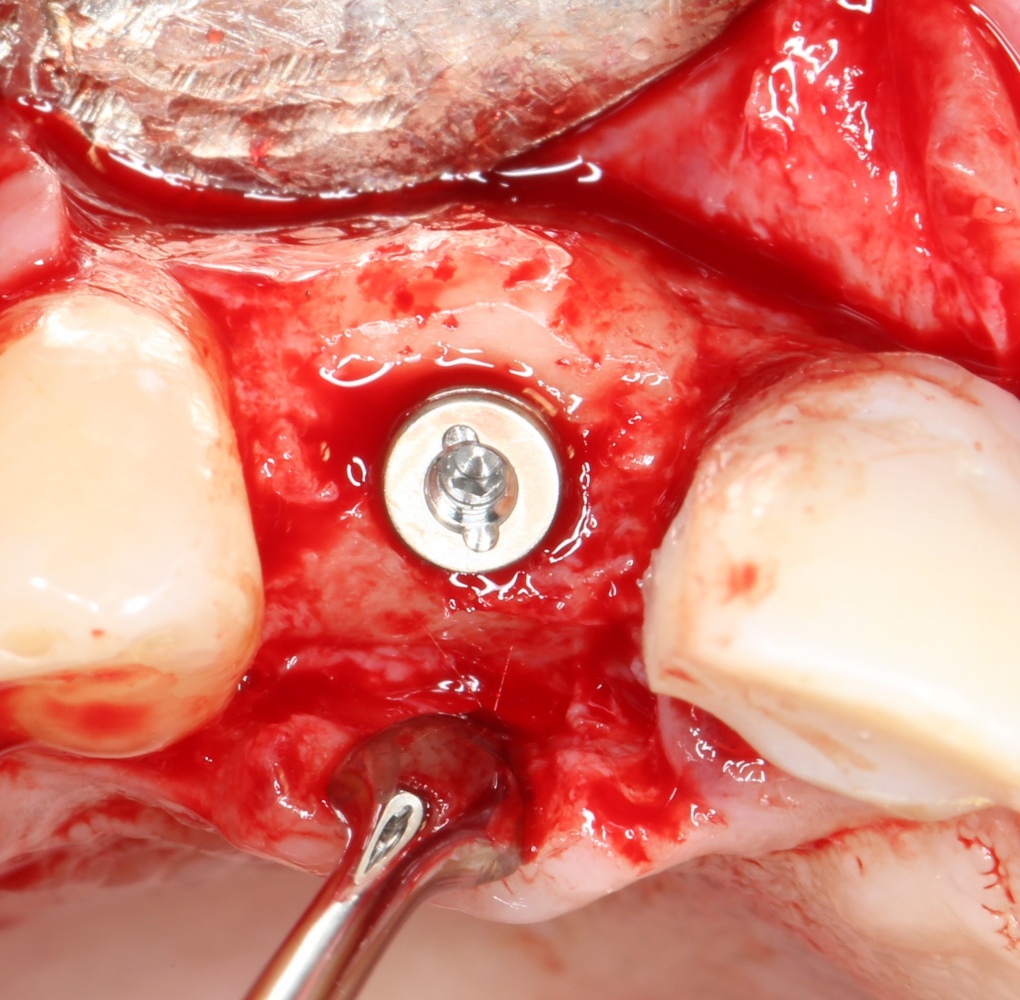

Я зафиксировал костный блок практически без адаптации на несколько винтов. Обрати внимание, что винты находятся в зоне, где не планируется установка имплантатов. Фиксация должна быть надежной, поскольку мне еще предстояла подготовка лунок для имплантатов. Трех винтов для этого вполне достаточно.

Дальнейшая адаптация костного блока свелась к сглаживанию острых краев. После чего я приступил к подготовке лунок и установке имплантатов.

Установка имплантатов.

Напомню, что для этой работы я выбрал субкрестальные имплантаты Ankylos C/X. Они прекрасно сочетаются с любым методом остеопластики.